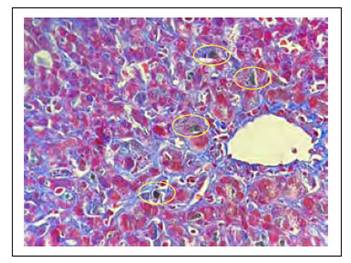

Los hallazgos histológicos en la biopsia hepática se muestran en las Figuras 1 a 6.

Figura 1 Con la tricrómica de Masson se evidencia colágeno joven, es decir que la tonalidad azul clásica del colágeno que se observa en la vena es más intensa que en las áreas sinusoidales, lo cual corrobora el hallazgo de necrosis en zona acinar 3. Resalta los tapones de bilis en los canalículos (circulo amarillo).